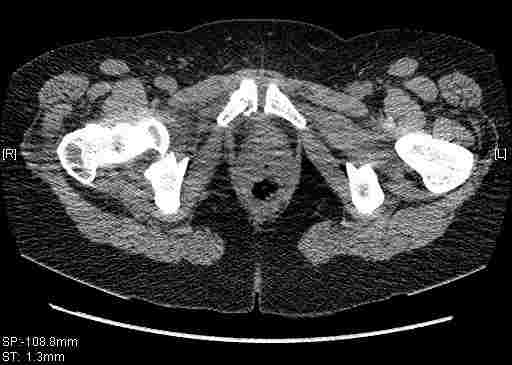

Удалось сегодня вывести пациентку в соседнюю больницу, где есть кт. Срезы сделаны только горизонтальные.